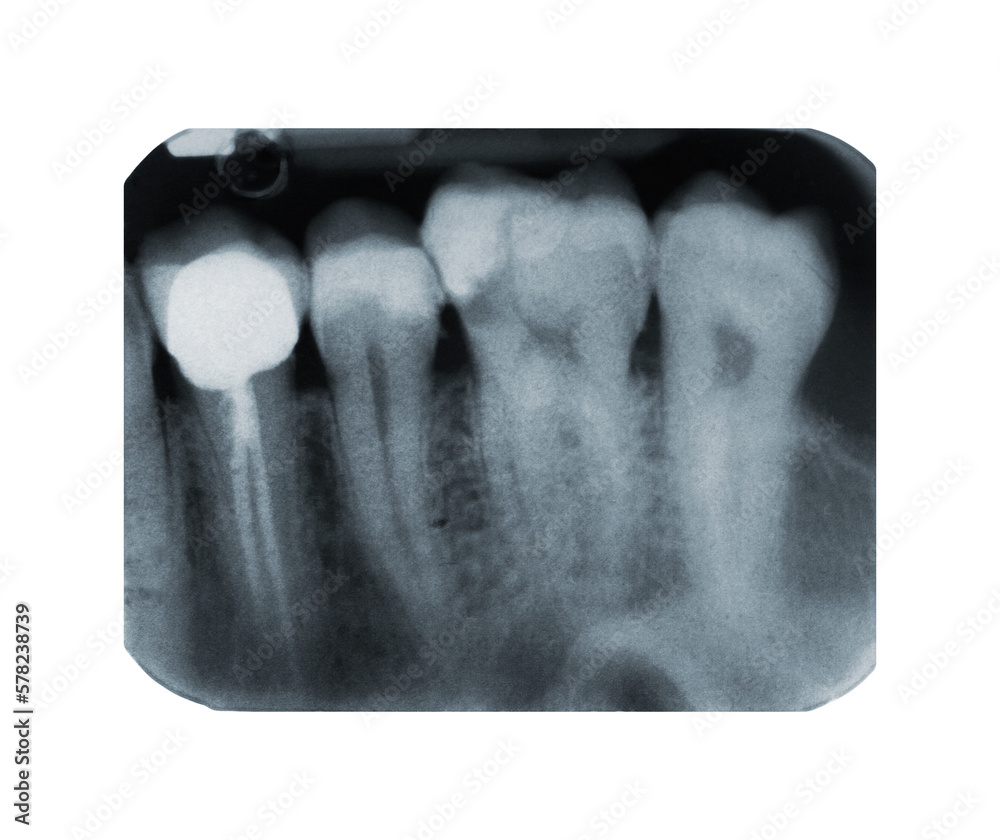

Tooth X Ray That Needs Root Canal . Dark spots at the tip of the tooth’s roots: These spots signify an infection in the bone near the tooth’s end, indicating that the pulp is diseased or dead. They may do other tests to determine if your tooth pulp is dead,. Numb the tooth and the area around it with local. 2nd stage of root canal. Once the need for a root canal is confirmed, local anesthesia is administered to numb the area and ensure your comfort during the procedure.

These spots signify an infection in the bone near the tooth’s end, indicating that the pulp is diseased or dead. 2nd stage of root canal. They may do other tests to determine if your tooth pulp is dead,. Numb the tooth and the area around it with local. Once the need for a root canal is confirmed, local anesthesia is administered to numb the area and ensure your comfort during the procedure. Dark spots at the tip of the tooth’s roots: